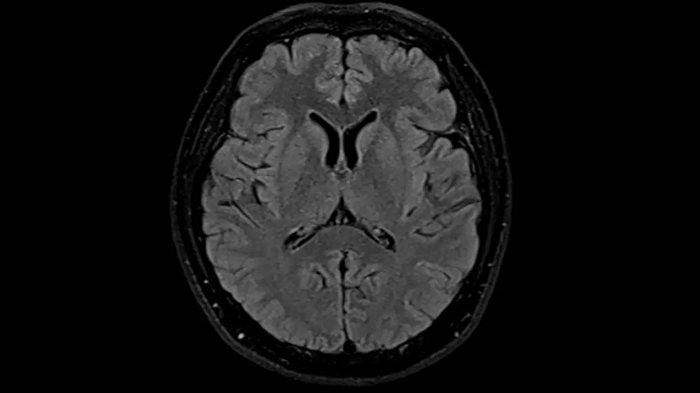

T2 TSE Dark Fluid with Deep Resolve

To produce high-resolution images, Deep Resolve, the Al-powered image reconstruction technology gets benefits from intelligent denoising and neural networks.

Deep Resolve Gain & Sharp

0.4 x 0.4 x 5.0 mm2

TA 4:32 min

MAC-ID: 7aaaa0195

MAC-ID: 7aaaa0195. Image Credit: Siemens Healthineers